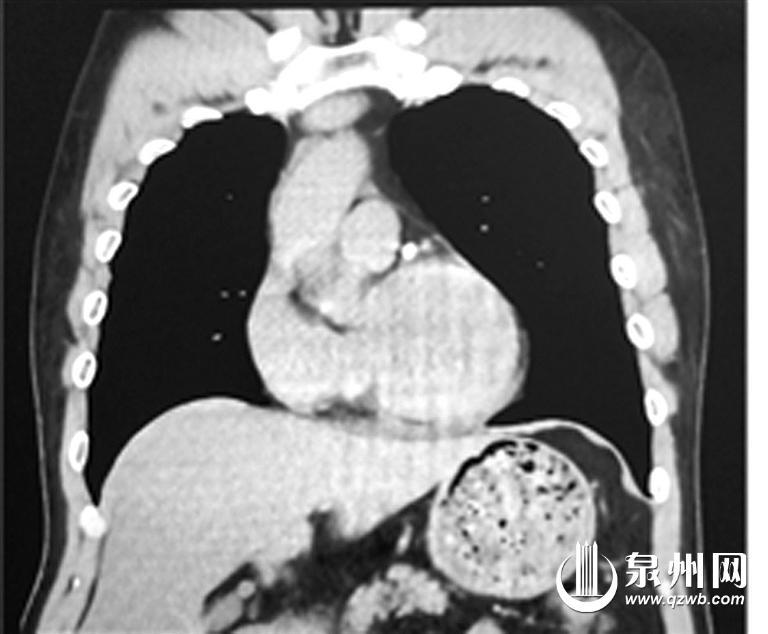

正常人(左)与“镜面人”CT影像对比

泉州市第一医院城东院区胃肠外科主任陈锦萍说:“正常来说,人的心脏在左侧,肝脏在右侧。但该患者从腹部到胸部,所有的脏器全部长反了,也就是所谓的‘镜面人’,即心脏、肝脏、脾脏、胆等器官的位置与正常人相反。在临床中,这种情况的发生率仅百万分之一。”